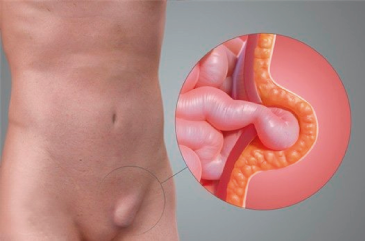

Hernias

Una hernia se presenta en alguna zona de debilidad de la pared abdominal, a través del cual protruye el contenido de la cavidad abdominal pudiendo ser un asa intestinal o tejido graso. Las hernias se manifiestan con dolor que se incrementa con el esfuerzo o movilización y zonas con aumentos de volumen cuyo contenido puede regresar al interior de la cavidad, requiriendo de manejo quirúrgico lo antes posible, ya que puede complicarse con la imposibilidad de retornar el contenido de la hernia hacia el interior sufriendo lesión de los órganos por falta de irrigación y por lo tanto que se requiera de cirugía de Urgencia. Las hernias se pueden presentar a diferentes niveles de la cavidad abdominal o pueden ser secundarias a procedimientos quirúrgicos previos, por lo que realizamos procedimientos quirúrgicos para la atención de:

- Hernias Umbilicales

- Hernias Inguinales

- Hernias Femorales

- Hernias Ventrales

- Hernias Incisionales

- Hernias de Pared Abdominal

Realizamos diferentes abordajes y técnicas para la reparación de los defectos herniarios llevando a cabo cirugía abierta o cirugía laparoscópica dependiendo de la valoración de cada caso, además de llevar a cabo la colocación de mallas para evitar la recurrencia. Además contamos con experiencia en el manejo de hernias ventrales grandes, en las que utilizamos diferentes métodos, toxina botulínica y diferentes mallas para lograr el cierre de la pared abdominal.

Hernia Umbilical